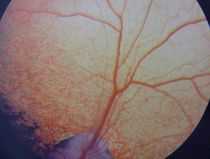

Wir führen in unsere Praxis verschiedenste Untersuchungen an und im Auge, wie z.B. die Augeninnendruckmessung mit einem elektronischen Tonometer (Tonopen) und die Darstellung des Augenhintergrundes mittels indirekter und direkter Ophthalmoskopie durch. Die Tränenproduktion wird mittels Schirmer Tränentest gemessen und Hornhautdefekte durch einen Fluoreszintest festgestellt. Mit einem Spaltlampenmikroskop untersuchen wir Hornhaut, vordere Augenkammer, Iris, Augenlinse und können auch kleinste fehlgestellte Wimpern (Distichien) erkennen. Mit einem speziell für Ultrachalluntersuchungen des Auges geeignetem Schallkopf (12Mhz) können wir das Innere des Auges sowie hinter dem Auge gelegene Prozesse wie Tumore oder Abszesse diagnostizieren.

Die Behandlung von grünem Star (Glaukom), der Keratokonjunktivitis sicca (trockenes Auge), der Uveitis u.a. sowie die operative Entfernung von Lidrandtumoren werden in unserer Praxis durchgeführt.